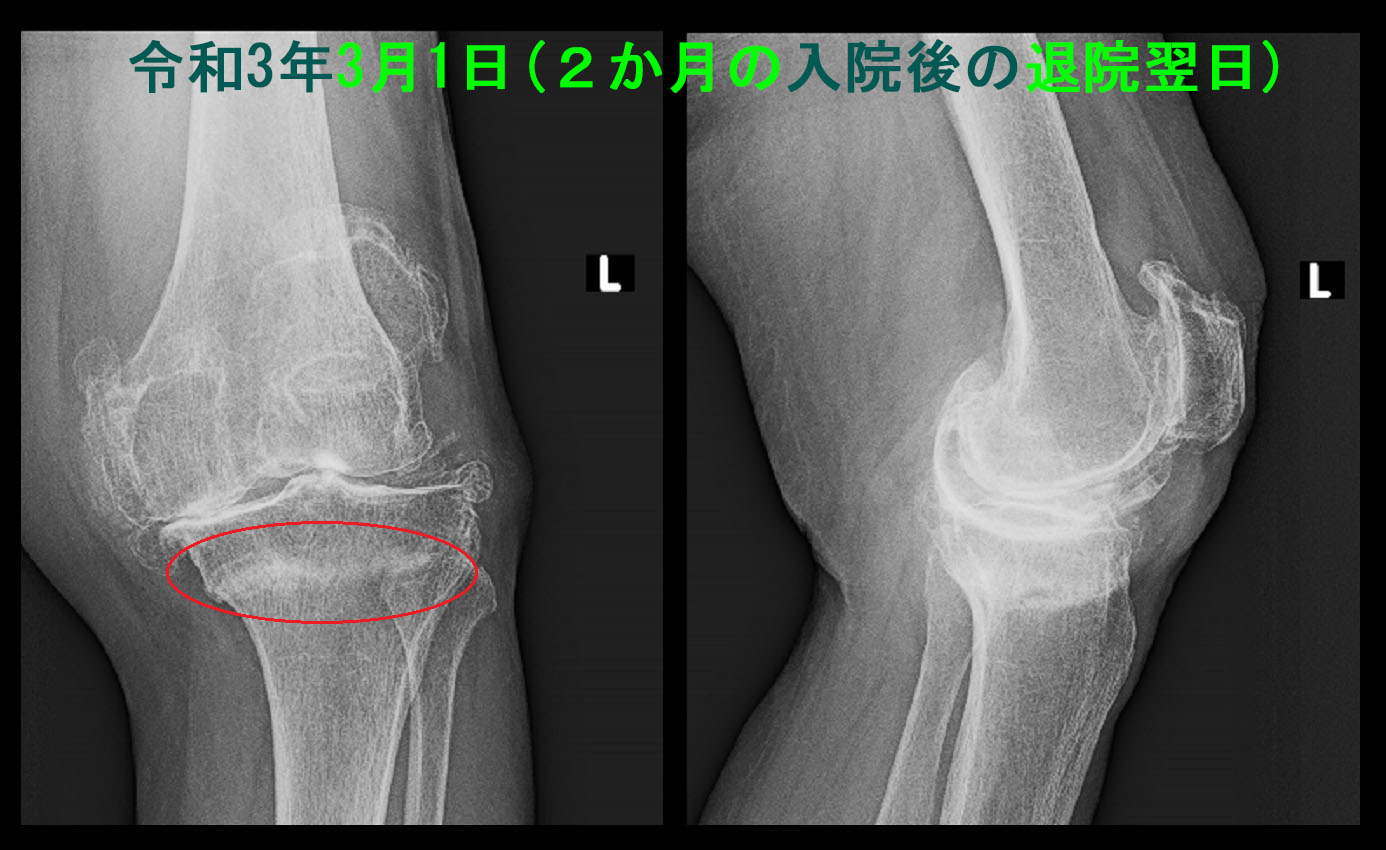

2月28日に退院し、当院には3月1日に受診されました。もともと右肩の変形性肩関節症の痛みがある方だったのですが、車いすの生活で腕を酷使したため右肩痛のため箸も使えないということでの受診でした。この時の左膝のレントゲン像です。

84才 2か月後Xp.jpg

骨折のあった赤丸部分は白く仮骨が形成されて、骨折が治癒していることが把握されます。